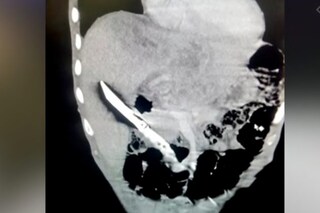

২০ সেন্টিমিটার দীর্ঘ ছুরি গিলে খেয়ে নিয়েছিলেন। তাও আবার ইচ্ছে করেই। তারপরেও কাউকে কিচ্ছুটি বুঝতে দেননি। শরীরে কোনও সমস্যা ছিল না। কিন্তু দিন দিন খাওয়ার পরিমাণ কমে যাচ্ছিল। সম্প্রতি পেটে ব্যথাও শুরু হয়। তারপরেই তাঁকে চিকিৎসকের কাছে নিয়ে যান পরিবারের সদস্যরা। চিকিৎসক এক্স রে করতেই চোখ কপালে ওঠে। দেখা যায় লিভারের মধ্যে রয়েছে বেশ বড় একটি ছুরি। সেটিকে ইতিমধ্যেই জটিল অস্ত্রোপচারের মাধ্যমে লিভার থেকে বার করেছেন দিল্লি এইএমএস (AIIMS)-এর চিকিৎসকরা। আপাতত ওই ব্যক্তির শারীরিক অবস্থা স্থিতিশীল।

হাসপাতালের বিশেষজ্ঞ চিকিৎসকদলের নেতৃত্বে ছিলেন গ্যাস্ট্রোএন্টেরোলজি বিভাগের প্রধান চিকিৎসক এনআর দাস। তিনি জানিয়েছেন, হাসপাতালে আগেও ধারালো জিনিষ খেয়ে নেওয়া রোগীর চিকিৎসা হয়েছে। তাঁদের মধ্যে কেউ বোর্ড পিন খেয়ে নিয়েছিলেন, কেউ সূচ আবার কেউ মাছ ধরার হুক। তাঁদের ক্ষেত্রে অস্ত্রোপচারের পরে রোগীরা সুস্থ হয়ে বাড়ি ফিরেছে। কিন্তু এভারে পুরো ছুরি খেয়ে নেওয়ার মতো ঘটনা বিরল। চিকিৎসক জানিয়েছেন, হরিয়ানার বাসিন্দা ২৮ বছরের এই যুবকটির ক্ষেত্রে সে ছুরিটি খাওয়ার পড়ে তা লিভারে গিয়ে আটকে গিয়েছিল। অস্ত্রোপচারের সময় সেটি লিভারের মধ্যে একদম চেপে বসেছিল। প্রায় ৩ ঘণ্টা ধরে চলে অস্ত্রোপচার। তারপরেই সেটি বার করা সম্ভব হয়েছে।

এ দিকে রোগীর পরিবারের তরফে জানা গিয়েছে, ওই যুবক মাদকাসক্ত। হাতের কাছে মাদক না পেয়ে ছুরিটি গিলে ফেলেছিল। চিকিৎসকদের কাছে সেই কথাই জানিয়েছে সে। তবে চিকিৎসকদের কাছে কেন এই অস্ত্রোপচার জটিল ছিল? চিকিৎসক এনআর দাস বলেন, ছুরিটি পিত্তনালী এবং মহা ধমনীর মধ্যে বিপজ্জনকভাবে আটকে ছিল। সেক্ষেত্রে কোনওভাবে হাত এদিক-ওদিক হলে মহাধমনী ক্ষতিগ্রস্ত হয়ে প্রবল রক্তক্ষরণে মৃত্যু হতে পারত রোগীর। ফলে অত্যন্ত সন্তর্পণে গোটা বিষয়টি করতে হয়েছে। চিকিৎসকরা খাদ্যনালীর দেওয়াল কেটে লিভার থেকে ছুরিটি বার করে এনেছেন।